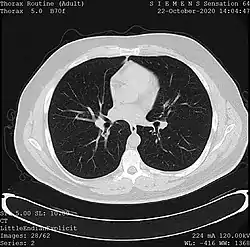

One frame of a CT scan of the chest showing the heart and lungs

• X-ray computed tomography (CT), or Computed Axial Tomography (CAT) scan, is a helical tomography technique (latest generation), which traditionally produces a 2D image of the structures in a thin section of the body. In CT, a beam of X-rays spins around an object being examined and is picked up by sensitive radiation detectors after having penetrated the object from multiple angles. A computer then analyses the information received from the scanner's detectors and constructs a detailed image of the object and its contents using the mathematical principles laid out in the Radon transform. It has a greater ionizing radiation dose burden than projection radiography; repeated scans must be limited to avoid health effects. CT is based on the same principles as X-Ray projections but in this case, the patient is enclosed in a surrounding ring of detectors assigned with 500–1000 scintillation detectors[13] (fourth-generation X-Ray CT scanner geometry). Previously in older generation scanners, the X-Ray beam was paired by a translating source and detector. Computed tomography has almost completely replaced focal plane tomography in X-ray tomography imaging.